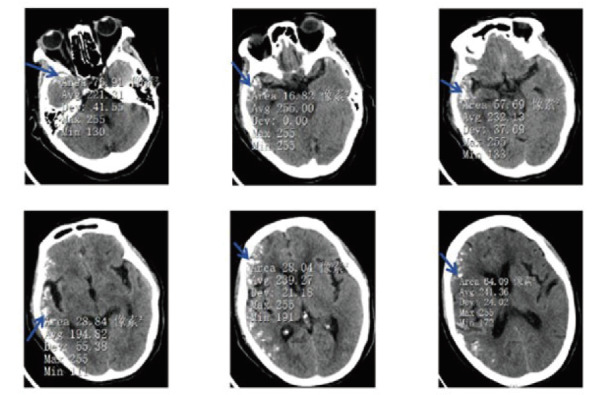

肺癌仍然是世界上最常见的恶性肿瘤之一。随着发病率的增加和医疗技术的发展,肺癌患者的总体生存期较以往有了明显延长。肺癌脑、脑膜转移的发病率也逐年上升,但肺癌脑、脑膜转移患者预后差,死亡率非常高,诊断主要依靠计算机断层扫描(CT)、磁共振成像(MRI)等影像学检查。但其影像学特征多样,特异性低,易误诊漏诊。因此,准确识别脑及脑膜转移灶并及时进行靶向治疗对改善患者预后至关重要。本文分析1例肺癌根治性手术后近7年长期随访无明显复发转移,但近5个月患者行为异常、意识受损、癫痫,头部CT及MRI发现脑内多发点状钙化的诊断与治疗。本文认为患者的精神和行为症状是在排除感染性疾病和自身免疫性脑炎治疗无效后,由肺癌脑、脑膜转移引起的,进一步病理活检和基因检测证实为表皮生长因子受体(EGFR) L858R基因突变的转移性肺腺癌,经奥西替尼靶向治疗后,患者症状得到明显改善。本文还在中国知网、万方、UpToDate、PubMed等数据库中检索了脑钙化的相关文献,发现脑钙化存在于多种疾病中,包括感染性疾病、遗传性和神经退行性疾病、血管疾病、代谢疾病和肿瘤。然而,脑钙化和脑膜转移往往被低估,随之而来的风险是误诊和延误治疗。因此,在既往有肿瘤病史的患者中,表现为脑钙化的脑和脑膜转移不应被忽视。

Lung cancer is still one of the most common malignant tumors in the world. With the increase of its incidence and the development of medical technology, the overall survival of lung cancer patients has significantly extended compared to before. The incidence of brain and meningeal metastases from lung cancer has also been rising year by year, but patients with brain and meningeal metastases from lung cancer have a poor prognosis and a very high mortality rate, and the diagnosis is mainly based on computed tomography (CT), magnetic resonance imaging (MRI) and other imaging examinations. However, the imaging features are diverse and the specificity is low, which makes it easy to be misdiagnosed and missed. Therefore, accurately identifying brain and meningeal metastases and timely targeted treatment is crucial for improving patient prognosis. This paper analyzed the diagnosis and treatment of a case of lung cancer with no obvious recurrence and metastasis in nearly 7-year long-term follow-up after radical lung cancer surgery, but the patient with abnormal behavior, impaired consciousness and epilepsy in the past 5 months, and multiple punctate calcifications in the brain found by head CT and MRI. This paper consider that the patient's mental and behavioral symptoms were caused by brain and meningeal metastasis of lung cancer after excluding infectious disease and ineffective treatment of autoimmune encephalitis, and further pathological biopsy and genetic detection confirmed the diagnosis of metastatic lung adenocarcinoma with epidermal growth factor receptor (EGFR) L858R gene mutation, and the patient's symptoms were significantly improved after targeted therapy by Osimertinib. This paper also searched the relevant literatures of brain calcifications in databases such as China National Knowledge Infrastructure (CNKI), Wanfang, UpToDate, PubMed, etc., and found that intracerebral calcifications exist in a variety of diseases, including infectious, genetic and neurodegenerative diseases, vascular diseases, metabolic diseases and tumors. However, brain calcification in brain and meningeal metastases are often underestimated, and the consequent risk is misdiagnosis and delayed treatment. Therefore, brain and meningeal metastases manifested as brain calcification should not be ignored in patients with a history of previous tumors.